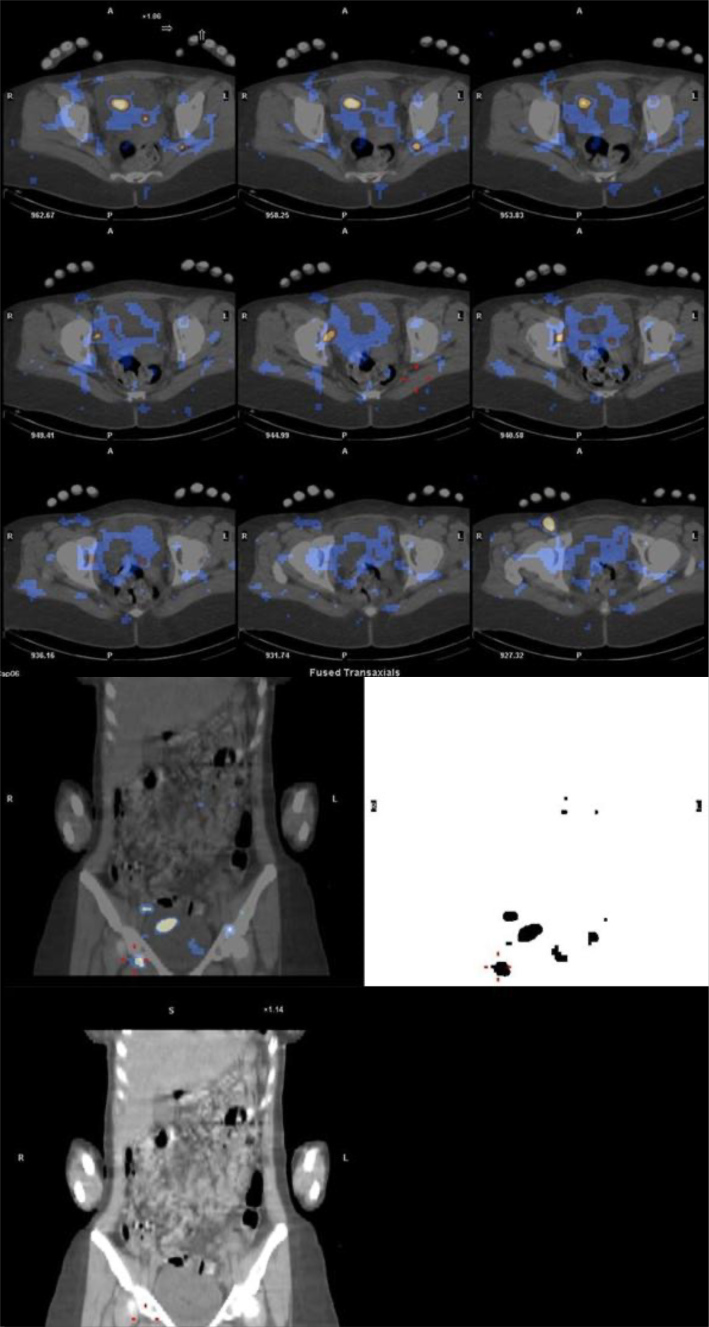

Chyluria, defined as the presence of chyle in urine, is a rare condition caused by an abnormal communication between the lymphatic system and the urinary tract. It can present with massive proteinuria and characteristic milky urine, mimicking nephrotic syndrome. We report the case of a 23-year-old woman with a history of seronegative ocular myasthenia gravis who developed progressive bilateral lower extremity oedema and intermittent nephrotic-range proteinuria despite normal serum albumin and lipid profiles. A renal biopsy, performed to investigate proteinuria, was complicated by a subcapsular hematoma. Shortly thereafter, the patient developed dysuria, urinary retention, and milky urine, leading to the diagnosis of chyluria. Imaging revealed thrombosis of the left iliac vein, associated with hereditary thrombophilia (heterozygosity for factor V Leiden and homozygous G20210A prothrombin mutation), prompting anticoagulation therapy. Lymphoscintigraphy suggested a lympho-vesical fistula and bilateral inguinal lymph node dysplasia. Conservative management, including urinary catheterization, fluid optimization, and dietary modifications with a low-fat, medium-chain triglyceride-enriched regimen, resulted in resolution of chyluria. At 6-month follow-up, there was no recurrence of symptoms, proteinuria improved, and anticoagulation was continued. This case highlights the importance of a multidisciplinary approach in managing rare presentations of chyluria, nephrotic proteinuria, and venous thrombosis.

Learning points: Chyluria should be considered in patients presenting with milky urine and proteinuria, especially after excluding glomerular pathology.Non-parasitic causes, such as trauma or iatrogenic procedures like renal biopsy, are increasingly recognized in non-endemic regions.Conservative management, particularly dietary modifications with medium-chain triglycerides can lead to significant clinical improvement without invasive interventions.